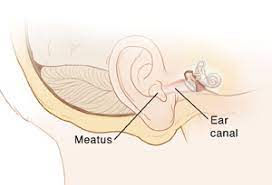

Overview

Package includes:

Days in hospital : 3 to 4 Days (For patient and one attendant)

Days in hotel : 7 Days (For patient and one attendant)

Room type in hospital : Shared

Room type in hotel : Private

Hotel category: Standard

Value added benefits of the Mastoidectomy and Tympanoplasty Including Meatoplasty: